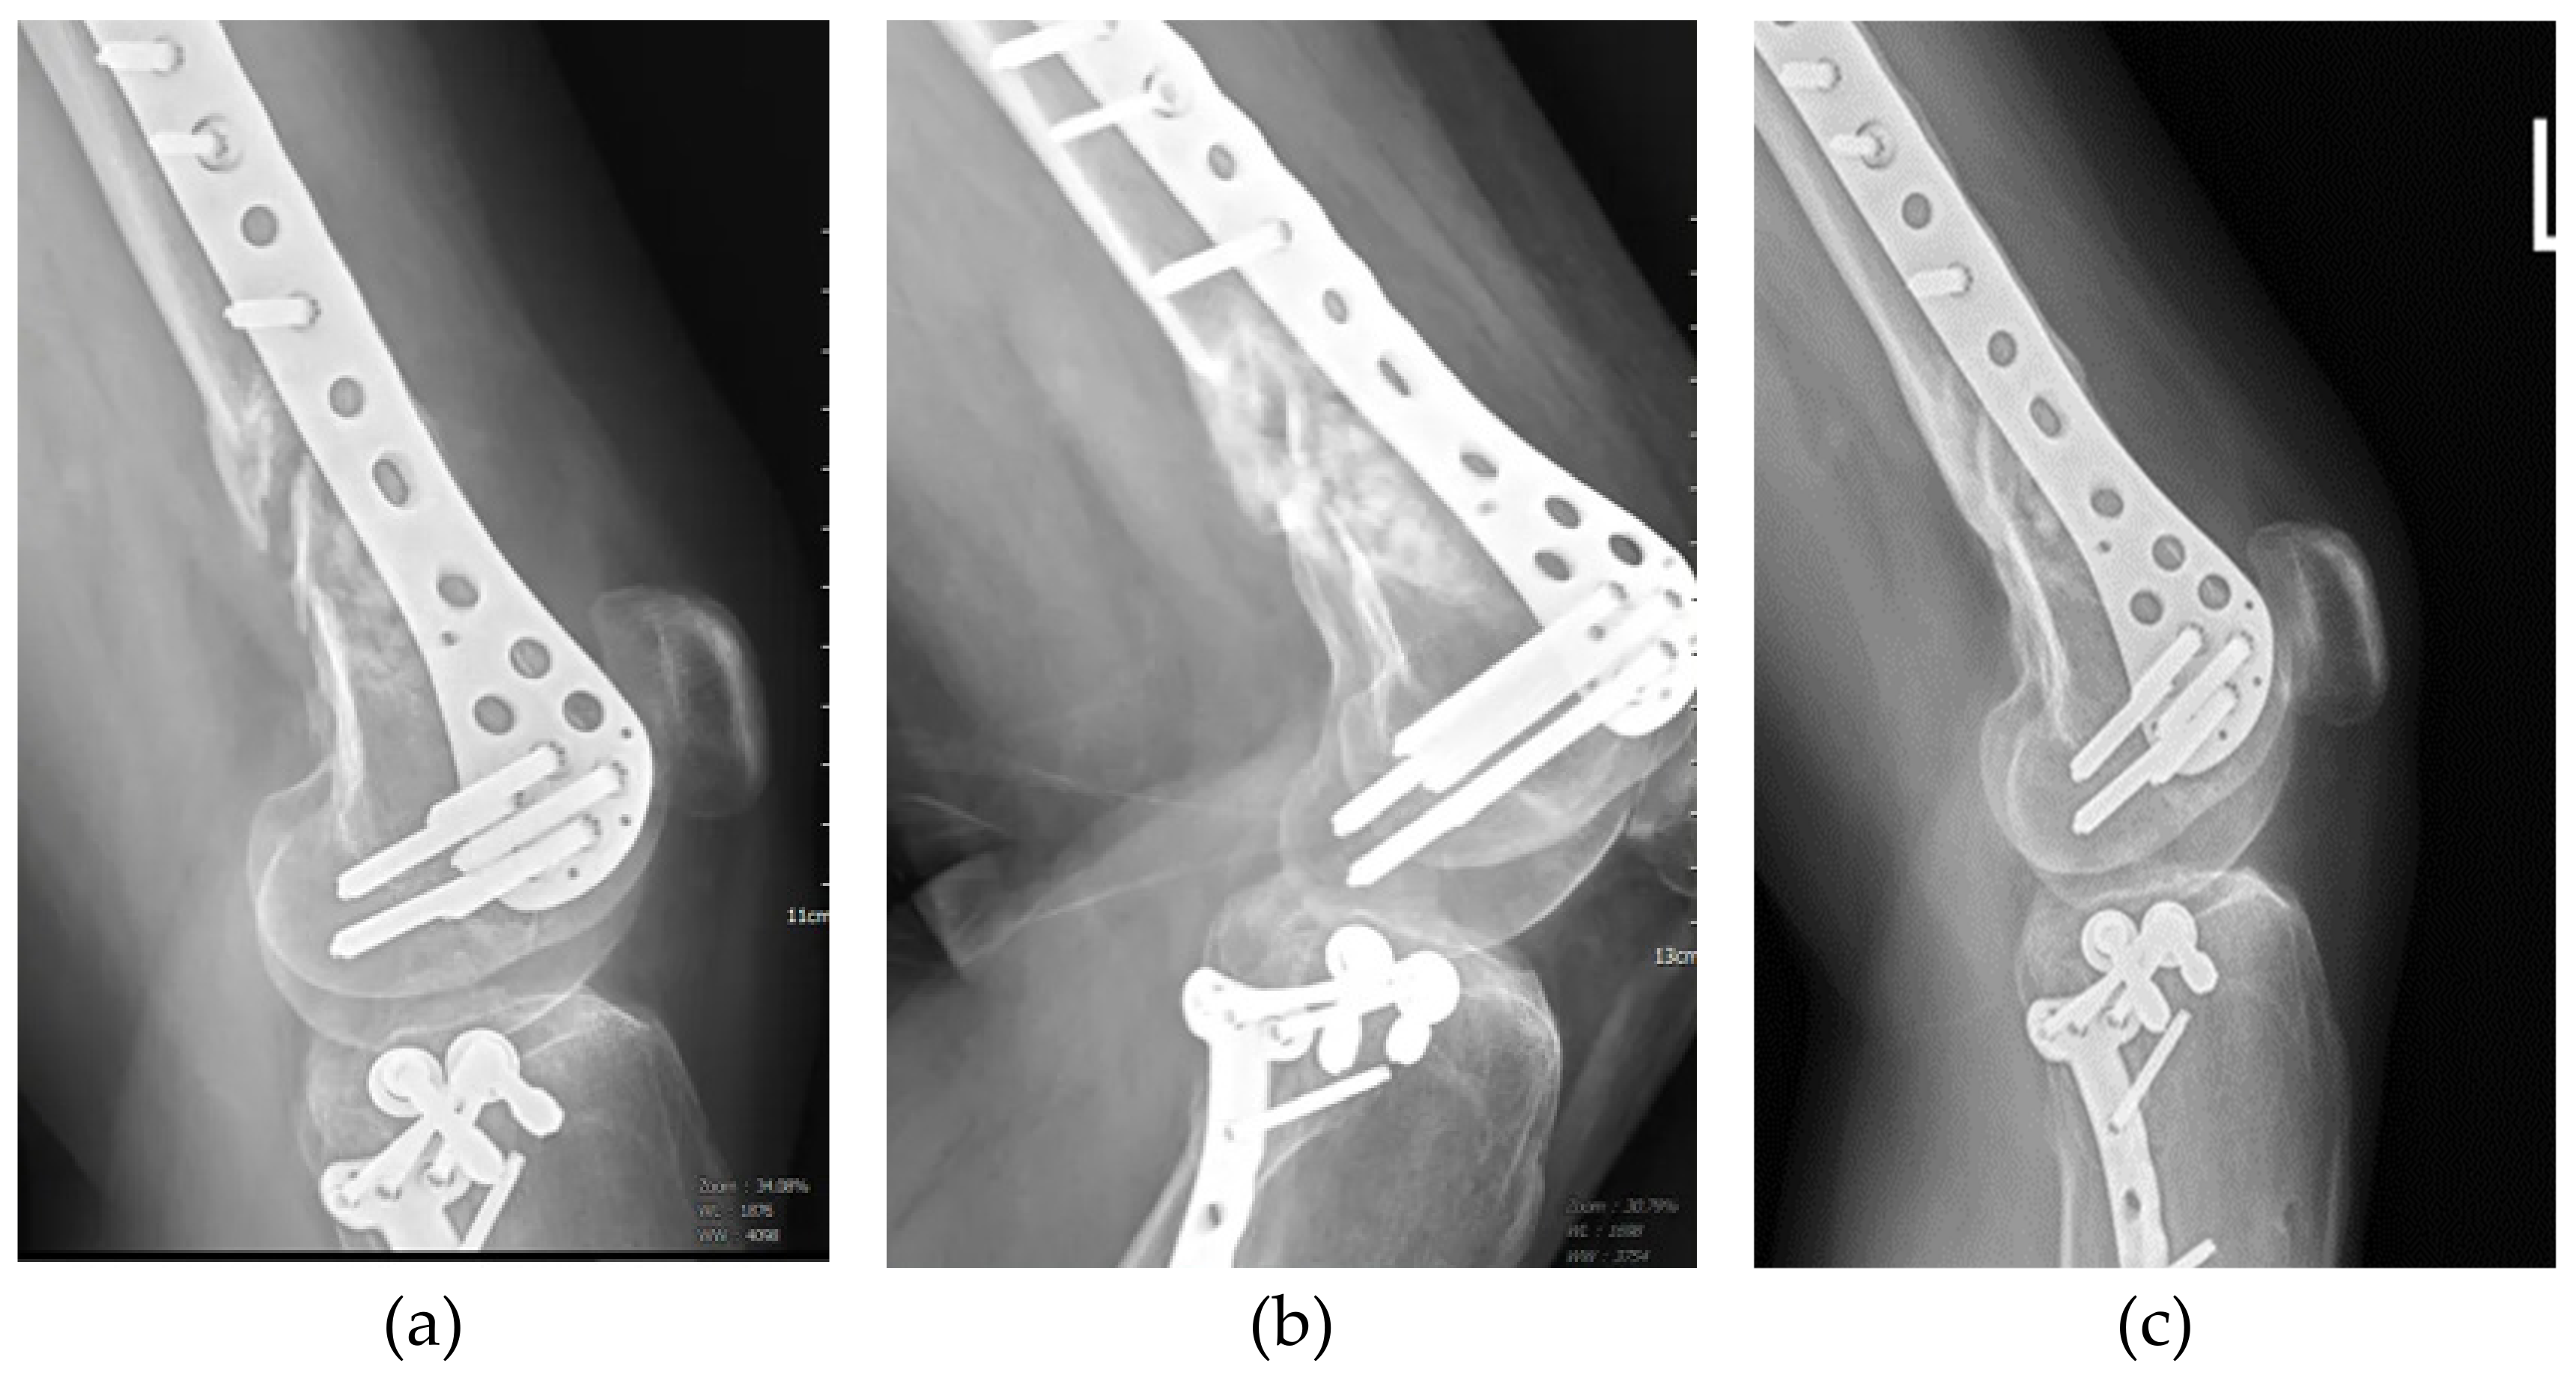

| 6 | 34 | Male | Left distal femur fracture | Non-union after ORIF | 9 | 3 | Union |

| 8 | 50 | Male | Left distal femur lateral condyle fracture | Non-union after ORIF | 36 | 2 | Union |